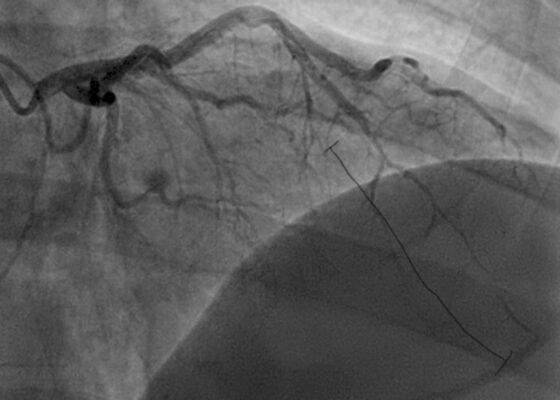

A Case Report of a 36-year-old Male Diagnosed with a Spontaneous Coronary Artery Dissection

DOI: https://doi.org/10.5070/M5.52022The initial ECG obtained from the patient shows subtle ST-segment elevation noted in leads I, aVL, and V2-V5, suggestive of pathology of the left anterior descending artery. The results of the catheterization revealed a spontaneous coronary artery dissection of the distal portion of the left anterior descending coronary artery, which can be seen in the image of the angiogram, with the diseased portion notated between the brackets.